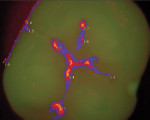

Historically, dentists around the world were taught that when an explorer stuck into the tooth, the patient had caries, and a restoration was mostly likely needed. Unfortunately, the dental explorer has only been shown to have a 24% sensitivity rate, which means that histological caries are actually discovered only 24% of the time when using this instrument, leaving 76% undiagnosed.5 Equally important is the fact that many patients were unable to truly understand this modality. Today, diagnostic technologies are much more visual and can provide what amounts to “a digital second opinion” by offering a different perspective than traditional clinical and radiological examination. Caries detection devices such as CamX Spectra (Air Techniques) and SOPROLIFE (Acteon) offer fluorescence-based technology that can help differentiate diseased tooth structures from healthy ones. The coloration spectrum allows patients to see areas of concern easily.

With respect to the CamX Spectra, patients can be shown a visual and numerical presentation (Figure 4). The device works by using light at a 405 nm wavelength to stimulate porphyrins—a byproduct of Streptococcus mutans. The porphyrins are essentially being used as a tracer to diagnose caries at an early stage, and this technology has been shown to have a 97% sensitivity rating.6

The SOPROLIFE emits light at a 450 nm wavelength, which excites a light fluorescence signal re-transmitted by dentin. When the dentin is healthy, a green hue is apparent on the digital image, and when the dentin is infected, a dark red hue is apparent. Unlike the CamX Spectra, no numerical value is paired with this image; however, research has shown that the Soprolife also has a high sensitivity rating (87%) when compared to the sensitivity of a dental explorer.7 Although both of these cameras focus on the diagnosis of occlusal caries, the SOPROLIFE has also been shown to be helpful in the diagnosis of approximal caries.